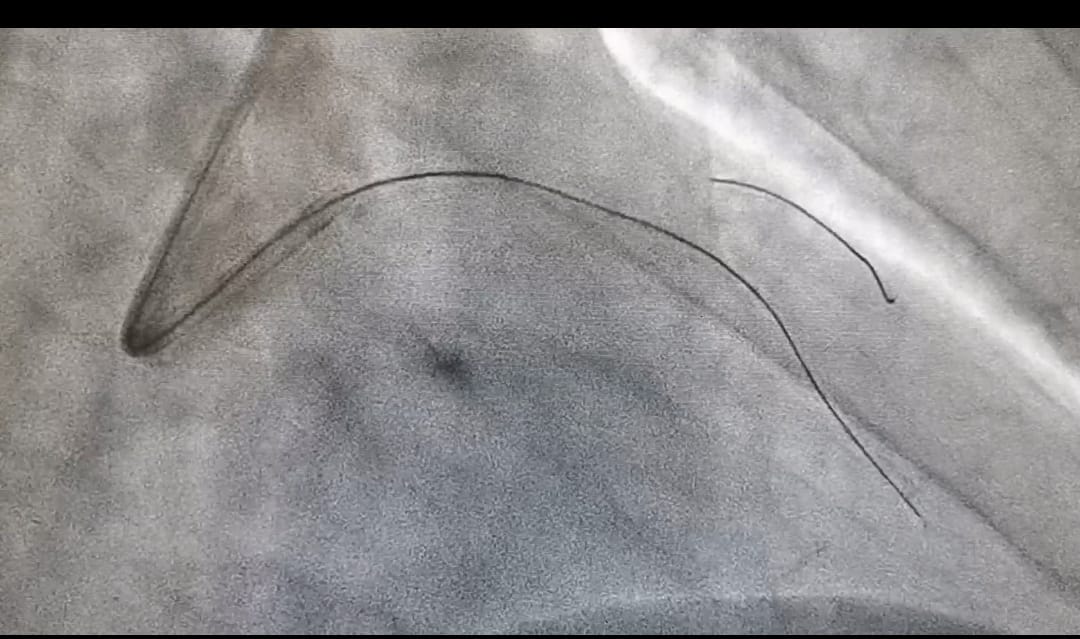

Grazie all’utilizzo di un microcatetere è possibile ripristinare il corretto afflusso di sangue al cuore nei pazienti affetti da occlusioni coronariche croniche totali (cto).

La nuova tecnica è stata utilizzata, tra i primi centri in Italia, nella Cardiologia dell’ospedale San Paolo di Bari. Si tratta di un intervento mininvasivo che evita di ricorrere all’unico approccio chirurgico del bypass aorto coronarico o, in alcuni casi, di non poter procedere con la rivascolarizzazione.

Ad eseguire l’intervento con microcatetere è stato il dottor David Rutigliano con il supporto dell’équipe medica e infermieristica del laboratorio di Emodinamica del San Paolo.

«La tecnica con il microcatetere – spiega Rutigliano – è una valida alternativa per il paziente che in passato non veniva trattato o poteva essere curato solo con bypass. In mani esperte garantisce buoni risultati (circa il 95% di successo) e con meno rischi periprocedurali».